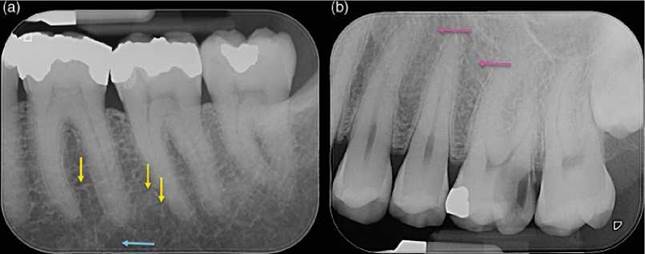

Figure 6.8 Periodontal ligament space. (a) Periapical radiograph of the mandibular right first, second and third molars. The predominantly horizontally oriented boney trabeculae (yellow arrows). Wider marrow spaces (blue arrow) may be mistaken for periapical radiolucencies. (b) The trabeculae in the maxilla (pink arrows) are thinner and more compact compared to those in the mandible.

Subtle alterations in the normal trabecular pattern of the cancellous bone are among the earliest indicators of the development of AP evident on conventional radiographs. The trabeculae begin to show evidence of disruption and disorganization (outside of normal functional modifications) around the apex (or other portal of exit) of the affected tooth (Figure 6.13). The area of trabecular disruption may be diffuse and difficult to demarcate from surrounding healthy tissue or, alternatively, it may be well-defined and easily differentiated from the adjoining bone. [20].

Figure 6.13 Incipient periapical bone loss. Periapical radiograph of the non-vital tooth 23. Demineralization of the bone around the apex of tooth 23 resulting in a "shotgun" appearance of the bone in the area (yellow arrows).